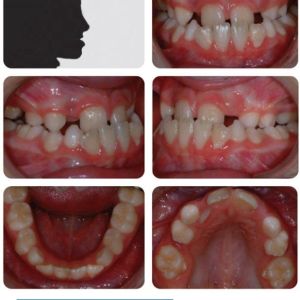

Phân tích case: Hình ảnh niềng răng thành công cho bệnh nhân 9 tuổi bị móm có bộ răng phức tạp

Bệnh nhân nữ 9 tuổi có sai khớp cắn hạng III trên nền xương hạng III từ nhẹ đến trung bình trên bộ răng hỗn hợp, phức tạp bởi:

- Độ cắn chìa âm (-3 mm)

- Chen chúc ở cả 2 cung hàm (nhưng hàm trên chen chúc nặng hơn vì mất sớm các răng hàm sữa thứ 2)

- Các răng cửa bên hàm trên chen chúc và lệch vòm miệng

- Mất khoảng ở vùng răng hàm nhỏ thứ 2 hàm trên